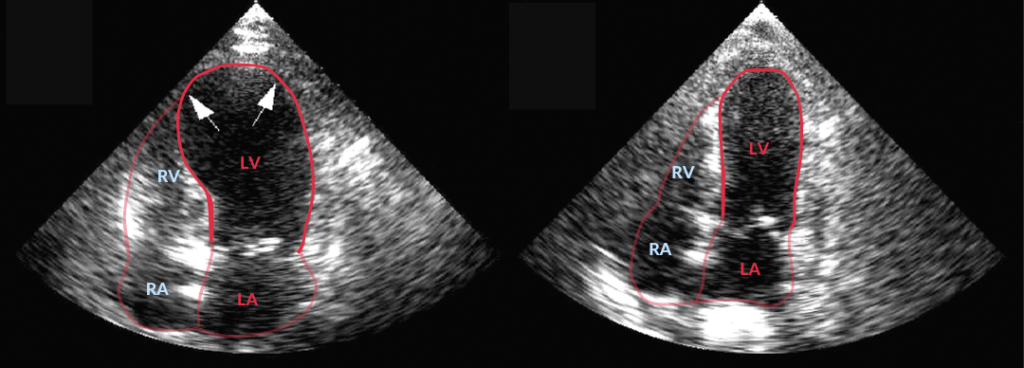

Zoals de term ‘transient’ in ‘transient apical ballooning) al suggereert, is de linkerventrikelfunctiestoornis tijdelijk, met herstel binnen een week tot enkele maanden. Hieronder zie je twee apicale vierkameraanzichten bij presentatie (links) en na herstel (rechts).